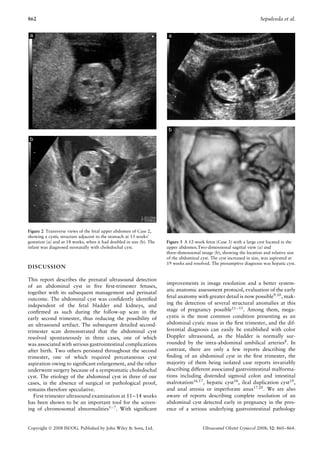

Figure 2 Transverse views of the fetal upper abdomen of Case 2,

showing a cystic structure adjacent to the stomach at 13 weeks’

gestation (a) and at 18 weeks, when it had doubled in size (b). The   Figure 3 A 12-week fetus (Case 3) with a large cyst located in the

infant was diagnosed neonatally with choledochal cyst.                upper abdomen.Two-dimensional sagittal view (a) and